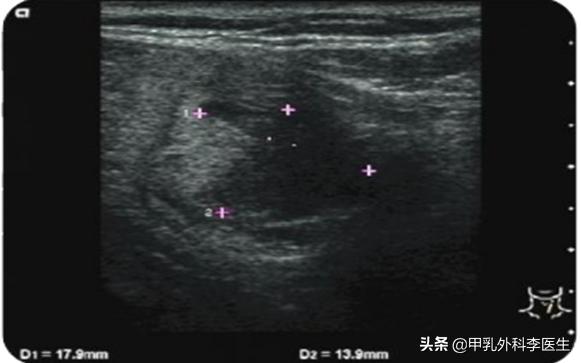

术后6个月肿块体积:1.8*1.4cm

从上图在术后的长期随访中甲状腺肿物体积明显缩小。